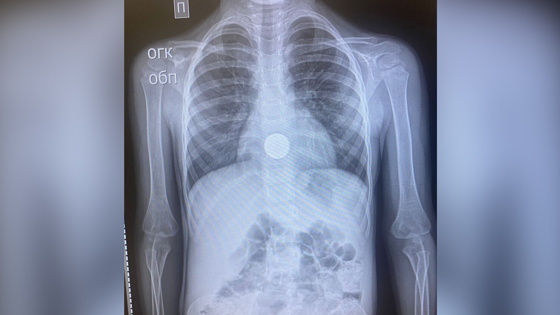

В Уфе четырехлетняя девочка случайно проглотила металлическую заколку в виде стрекозы, ее экстренно доставили в больницу скорой медицинской помощи. Об этом сообщается в Telegram-канале Минздрава Башкирии.

В ходе обследования ребенка медики обнаружили в желудке инородный предмет — металлическую заколку в форме бабочки, которую девочка проглотила, играя дома.

Операцию пришлось проводить под общим наркозом, инородный предмет удалили за 10 минут. Сейчас жизни и здоровью пострадавшей ничего не угрожает, девочка пока находится под медицинским наблюдением.